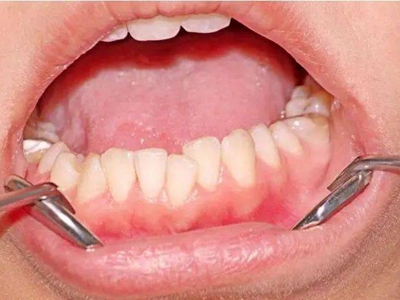

慢性龈炎的病损部位一般局限于游离龈和龈乳头,以前牙区为主,尤其以下前牙区最为显著,患者常因刷牙或咬硬物时牙龈出血而就诊。游离龈和龈乳头颜色变为鲜红或暗红色,病变较重时炎性充血可波及附着龈。龈缘变厚,龈乳头圆钝肥大,可增生呈球状,覆盖牙面。牙龈松软脆弱,缺乏弹性。

当牙龈以增生性反应为主时,龈缘和龈乳头呈坚韧的实质性肥大,质地较硬而有弹性。龈沟液量增多,还可能出现龈沟溢脓现象。